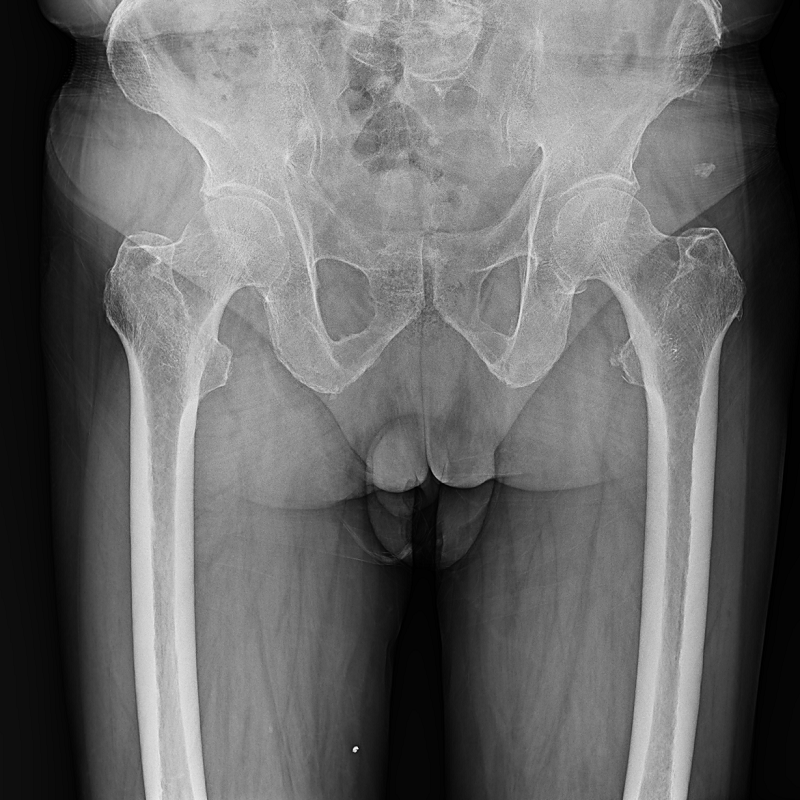

●呈現全下肢或全脊柱圖像

●在脊柱及下肢畸形矯正手術治療中,為術前方案制定和術后復查提供精準測量

●有效解決傳統X光片不能一次成像問題,為患者提供更加優質的醫療服務